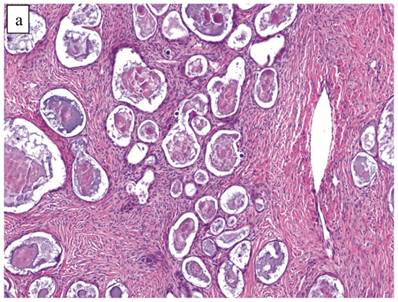

The clinicopathologic features with respect to age, stage, bilaterality, tumor size, and gross appearance are shown in Table 1. Histologically, the tumors contained a background of AF and exhibited greater glandular crowding as well as more variation in size and shape of glands, including cystic dilatation, compared with AFs (Fig. 2A). Occasional glands showed slightly more stratification of the epithelium (2-4 layers) but generally did not have substantial architectural complexity, such as papillary, solid, or cribriform patterns. The nuclei were mostly small, uniform, and flat to round but occasionally had mild nuclear enlargement and slight hyperchromasia; nucleoli, if present, were usually small (Fig. 2B).

Atypical proliferative (borderline) clear cell tumor. (A) The glands show a greater degree of crowding and variation in size and shape compared with clear cell adenofibroma. (B) The glands in many areas are lined by flat non-atypical cells. (C) Focal notable nuclear atypia is present in the glandular epithelium.

Only one case had mitotic activity (1 MF/10 HPFs). Notable nuclear atypia was focally present in 11 (27%) cases (Fig. 2C); however, such foci lacked associated stromal alterations and recognizable forms of invasion, such as an haphazard infiltration of glands, glandular confluence, mitotic activity within glands, or the conventional appearance of clear cell CA.